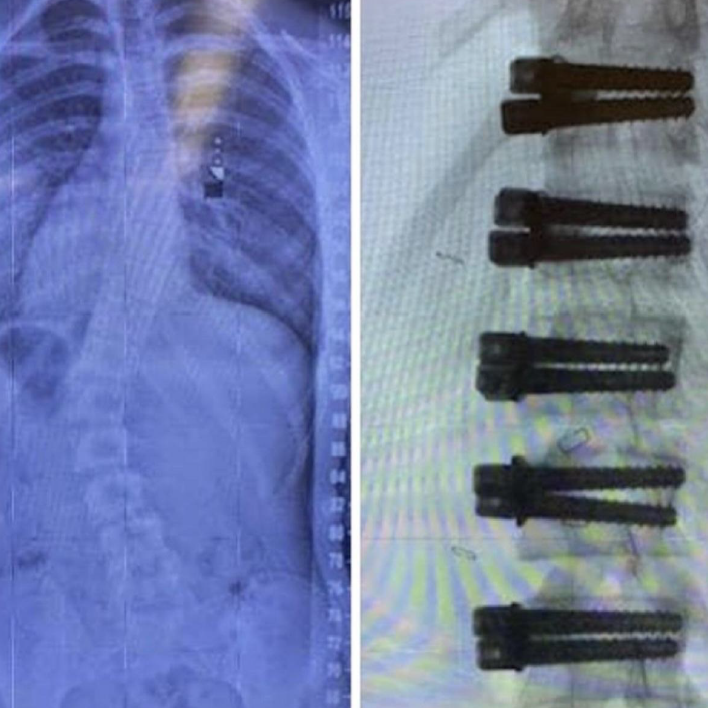

At first I thought my only options were to get a brace or spinal fusion. We went through the process of getting a brace only for me to completely give up after a day. I remember walking into the dance studio that day with my brace on crying because I just wanted to feel normal. We then tried physical therapy for several weeks but that method unfortunately did not give us the results we needed or any pain relief. After meeting with a doctor to discuss fusion my mom knew she needed to do some more research on other treatments because she wanted to make sure that my future quality of life and dancing would be the best it could possibly be. Fortunately she found the Vertebral Body Tethering procedure with Dr. Lonner in New York City.

After my initial appointment and deciding we were going to follow through with this treatment plan I was so upset at my parents. I knew they were looking out for me by making this decision but I was so scared that I chose to be angry. Looking back on it now, I am so incredibly thankful that they made that decision for me. Five years later and I would do it all over again if I had to. The providers at Mount Sinai Hospital were absolutely amazing. Now the recovery process wasn’t easy but I know the hard part of taking that leap of faith was already over. With my amazing support systems and my drive to be the best dancer and person I could be, I held my head high through the ups and downs of recovery. After my six weeks were up and I was cleared for movement, I immediately found myself back in the dance studio and was fully dancing on the competition stage that season and even the ones after.